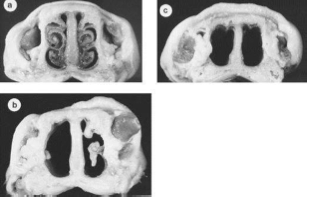

Note on image: KNOW THESE IMAGES. B and C show pig after infection when there has been erosion of nasal turbinates

Dermonecrotic toxin- destruction of turbinates in atrophic rhinitis

Atrophic rhinitis is associated with what two bacteria?

Bordetella Bronchiseptica and Pasteurella Multocida